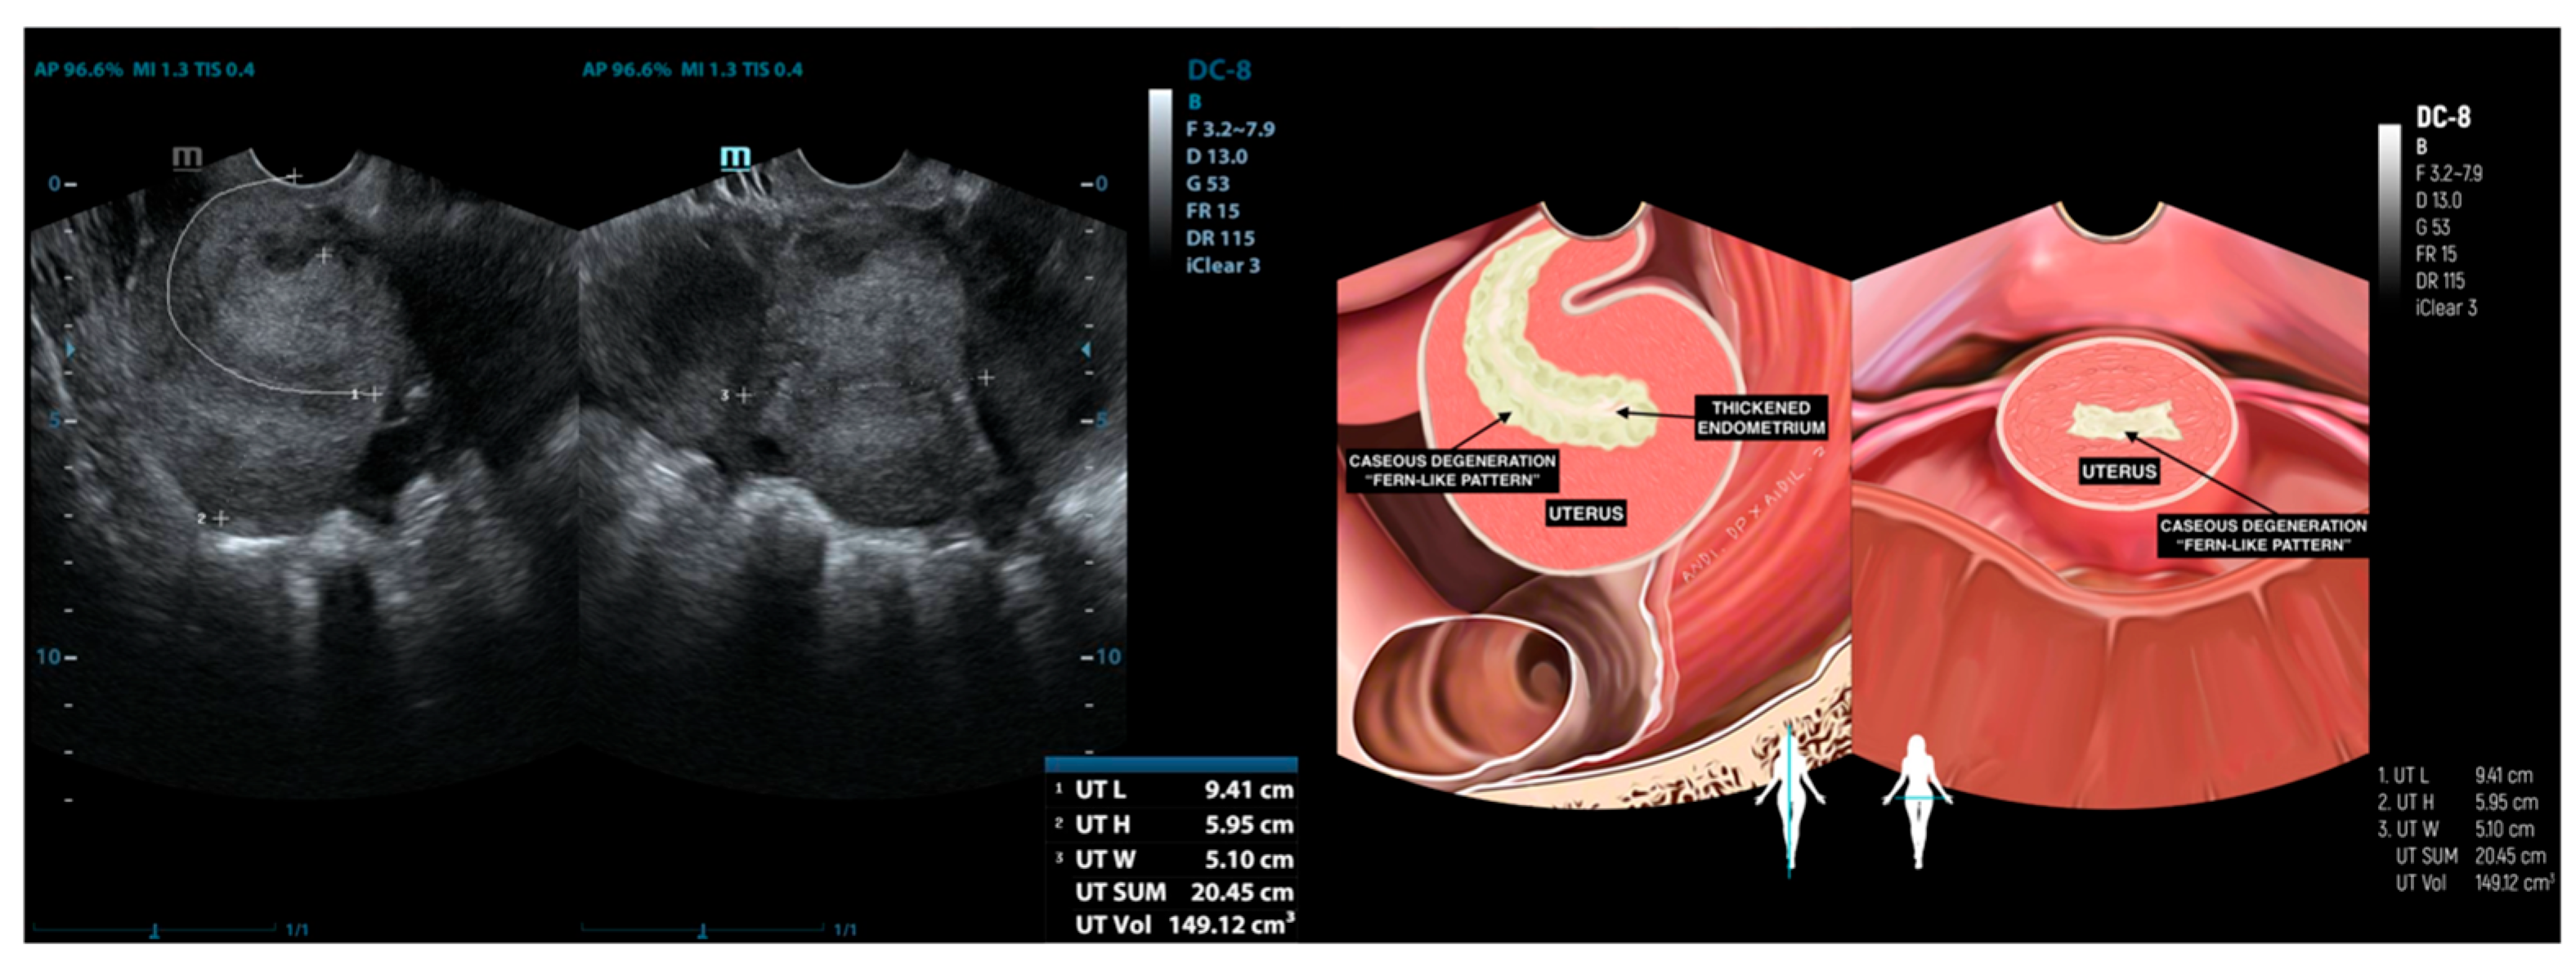

| 3 | IO (31) * | Caseous degeneration on the surface | Adhesion complex | Normal | Adhesion complex | Normal | (−) | Caseous degeneration on the surface of rectosigmoid colon and small bowel |

| 4 | SMK (29) * | Caseous degeneration on the surface. Complex fluid behind uterus | Normal | Not visualized | Adhesion complex with left fallopian tube | Hydrosalpinx | Complex fluid in cavum of Douglas with caseous degeneration | Caseous degeneration on the surface of rectosigmoid colon |

| 12 | DR (24) | Complex fluid in uterine cavity (10.98 mm) | Normal | Hydrosalpinx | Adhesion | Normal | (−) | (−) |